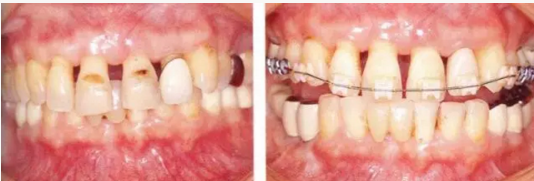

在正畸治療結(jié)束后仍然存在open contact的病例

▲圖15-1,2

在正畸??漆t(yī)生處接受了正畸治療,雖然上頜正畸治療已經(jīng)完成,但由于磨牙區(qū)的邊緣嵴不整齊而導(dǎo)致牙體之間存在空隙。要想在這個狀態(tài)下護理牙周組織以及咬合狀況是非常困難的。由此可見,在治療時,正畸專科醫(yī)生與全科口腔醫(yī)生保持目標一致是非常重要的。